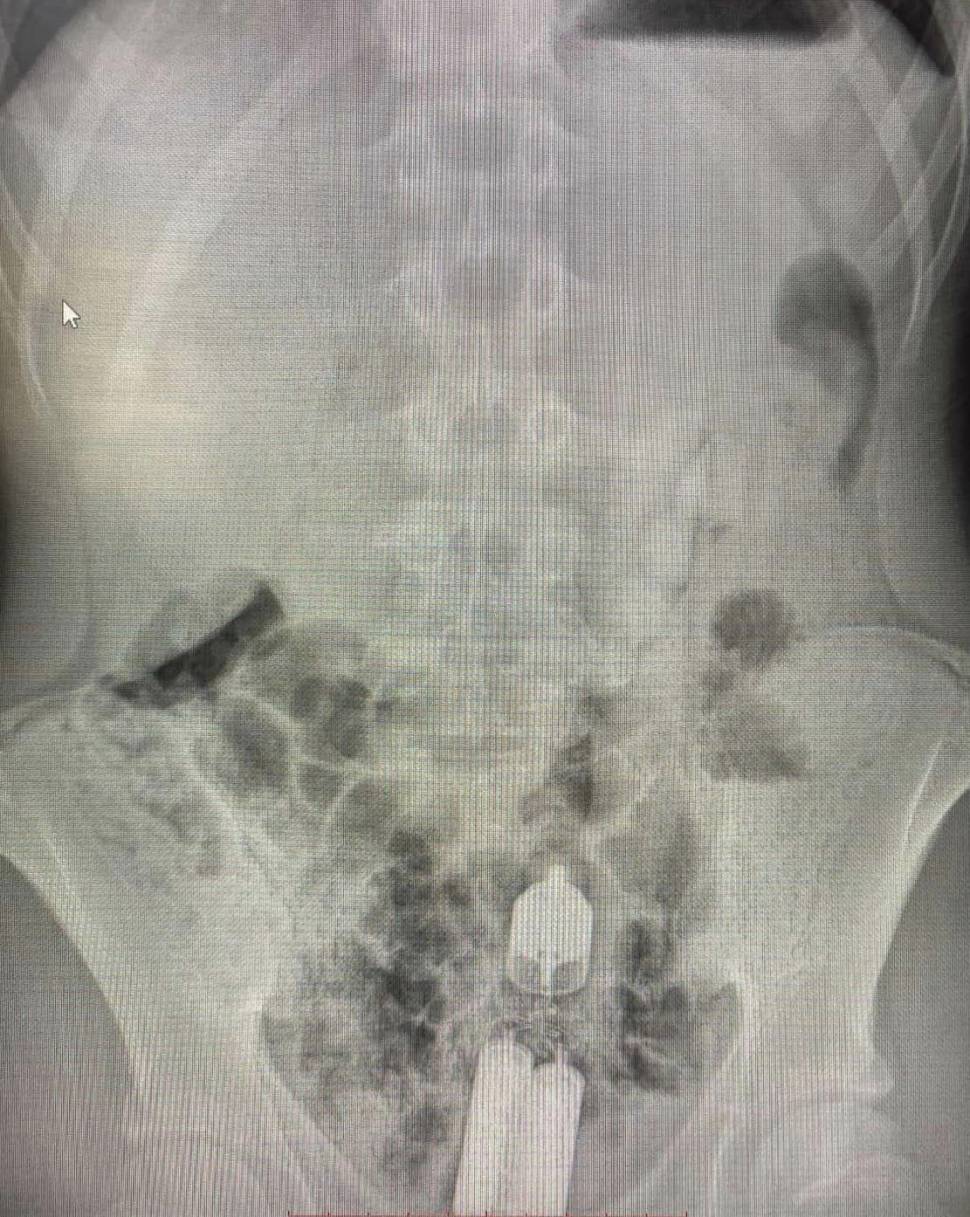

Один із останніх таких випадків стався з 16-річним хлопцем, у животі якого лікарі виявили вібратор. Три години вібратор продовжував працювати всередині пацієнта, приводячи до дискомфорту, болю в животі та кровотечі.

Подібні випадки є дуже небезпечними для здоров’я пацієнтів. Сторонні предмети можуть призвести до запалення кишківника, перфорації, сильної кровотечі та перитоніту.

У таких випадках слід негайно звернутися по медичну допомогу до лікарні, а не намагатися допомогти собі самостійно. Чим швидше фахівці приберуть сторонній предмет, тим більше шансів уникнути тяжких наслідків.